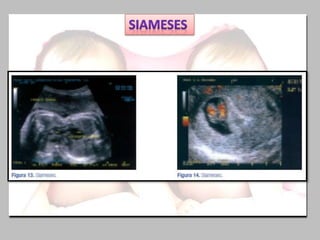

Los dos embriones

Comparten parte del

cuerpo, además de la

Placenta y bolsa.

Nombre Sitio de unión

Prosopópagos Cara

Cefalópagos Cabeza

Toracópagos Torax y región Supraumbilical

Onfalópagos Región Umbilical

Ileópagos Región Infraumbilical

Craneópagos Parietales y Occipitales

Pigópagos Región Sacrocoxígea

Isquiópagos Región Isquiática

Los dos embriones Compartenparte del cuerpo, además de la Placenta y bolsa. Nombre Sitio de unión Prosopópagos Cara Cefalópagos Cabeza Toracópagos Torax y región Supraumbilical Onfalópagos Región Umbilical Ileópagos Región Infraumbilical Craneópagos Parietales y Occipitales Pigópagos Región Sacrocoxígea Isquiópagos Región Isquiática